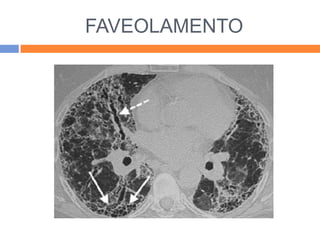

FAVEOLAMENTO

   Indica fibrose pulmonar com retração

compensatória do parênquima adjancente;

   Múltiplas causas, de acordo com o padrão de

acometimento;

   Boa indicação para TCAR;